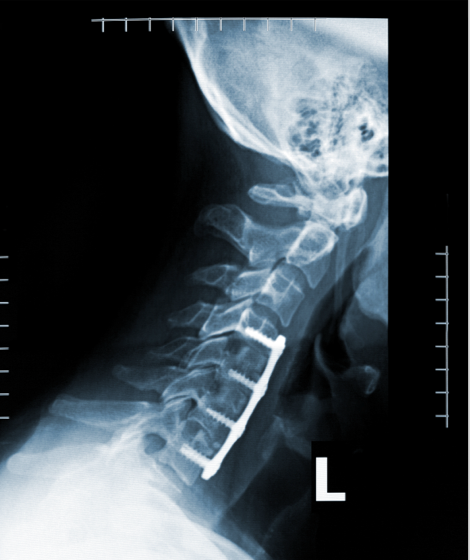

treatment

Imaging of IET’s again involves contrasted MRI of the cervical spine. In all but the largest tumors the surgical approach is via laminectomies with or without fusion and instrumentation depending on the extent of bone removal and the concern for post-operative kyphosis and instability. Unlike astrocytomas, the primary goal of surgical treatment of meningiomas and nerve sheath tumors is complete resection. Intraoperative neuromonitoring, laser, and ultrasonsic aspiration as well as microsurgical techniques are mainstays of surgery. Expected post-op neurologic deficits are less than 10% with modern surgical monitoring and techniques; in addition to usual concerns, post-op complications again include poor wound healing, meningeal inflammation, and cerebrospinal fluid leak.